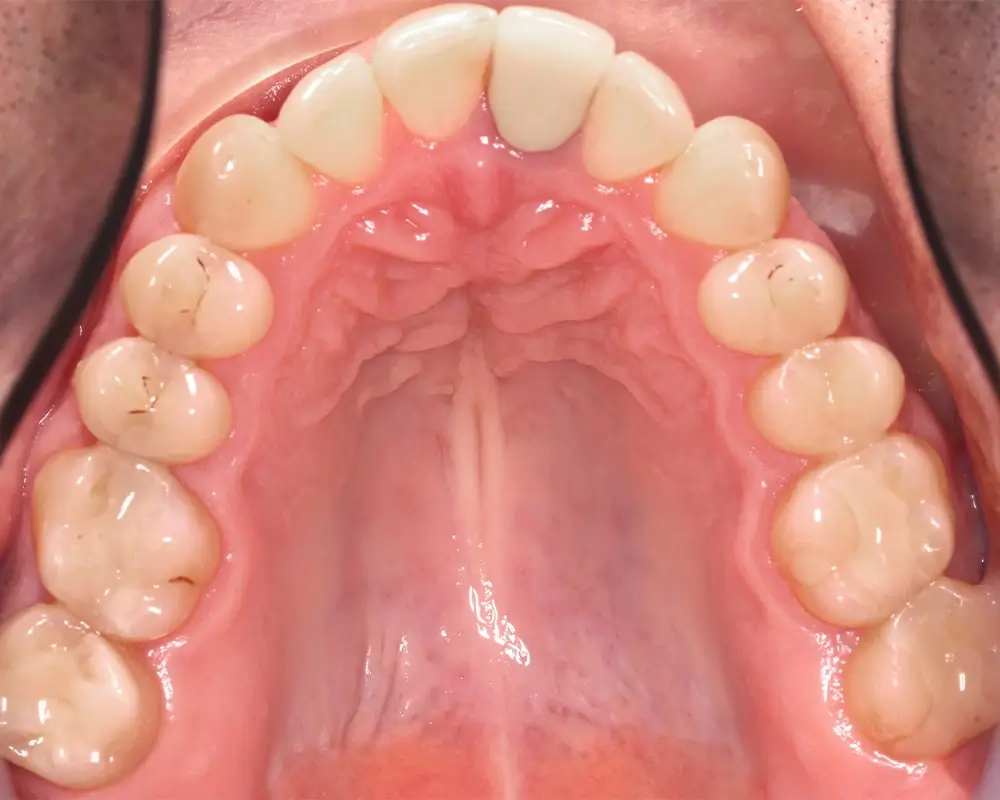

Мезиальный прикус - Кейс 7

Эффективность устранения дефекта прикуса посредством элайнеров FlexiLigner.

Количество кап ВЧ

Результаты лечения